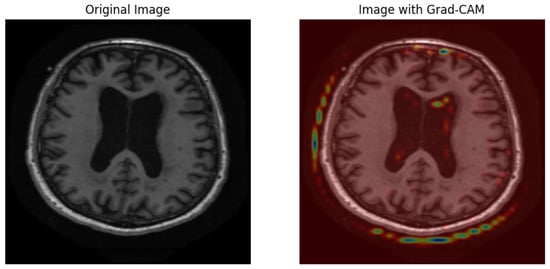

5.1.7. Grad-CAM Results

5.2.7. Grad-CAM